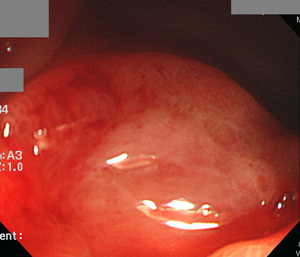

3³â Àü ³»½Ã°æ. Ulcer scar.

½ÊÀÌÁöÀå±Ë¾ç Àç¹ß ÃâÇ÷. UBT (+)